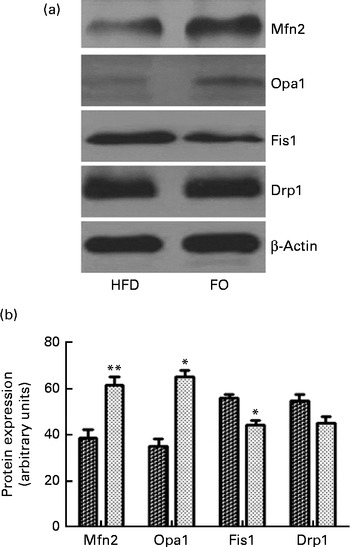

ApoE− / − mice fed FO had a higher level of mitochondrial fusion proteins, including Mfn2 and Opa1 (both P< 0·05), than HFD-fed mice. Conversely, FO-fed mice had lower protein expression levels of Fis1 than HFD-fed mice (P< 0·05). There was no significant difference in the protein expression levels of Drp1 between the two groups (Fig. 4(a) and (b)). ApoE− / − mice in the FO group had higher complex I–IV activities compared with those in the HFD group (P< 0·05). Conversely, mice in the FO group had lower complex V activity than those in the HFD group (P< 0·05). Complex III activity was similar between the two groups (Table 2).

Fig. 4 Mitochondrial fusion and fission protein expression in the aortas. (a) Representative Western blotting images. β-Actin is a comparative control. (b) Densitometric quantification of the expression levels of mitofusin-2 (Mfn2), optic atrophy-1 (Opa1), fission-1 (Fis1) and dynamin-related protein-1 (Drp1). Fusion proteins include Mfn2 and Opa1; fission proteins include Fis1 and Drp1. Values are means of three experiments, and the bands are representative of twelve mice, with standard deviations represented by vertical bars. Mean value was significantly different from that of the high-fat diet (HFD; ![]() ) group: * P< 0·05, ** P< 0·01. FO

) group: * P< 0·05, ** P< 0·01. FO ![]() , high-fat diet enriched with 10 % fish oil.

, high-fat diet enriched with 10 % fish oil.

The mitochondria dynamically undergo fusion and fission processes, which are critical for the release of cytochrome c and are associated with increased cellular apoptosis( Reference Leboucher, Tsai and Yang 43 ). We hypothesised that FO would affect mitochondrial morphology by inducing alterations in fusion proteins, such as Mfn1 and Mfn2, and fission proteins, such as Drp1. Our findings demonstrated that the expression of the mitochondrial proteins Mfn2 and Opa1 was higher in the aorta of apoE− / − mice fed FO than that of HFD-fed mice. Conversely, FO supplementation resulted in a significant decrease in the expression of the fission protein Fis1 in the aorta. These findings suggest that FO-induced alterations in mitochondrial dynamics improved endothelial cell function. However, the underlying mechanism for this observation is unknown and warrants further study.